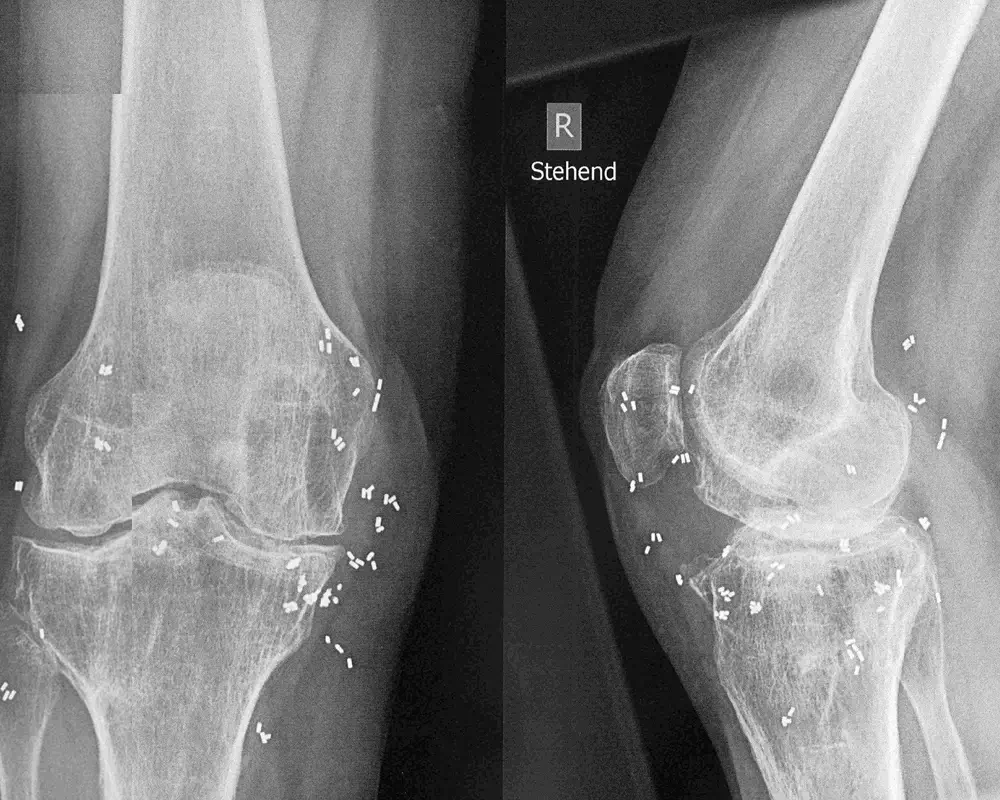

Kniegelenke

Gezielte Entzündungshemmung für mehr Stabilität und Mobilität.

Nach ausführlicher Diagnostik und Beratung werden unter lokaler Betäubung winzige 1–2 mm lange Segmente aus 24-karätigem Golddraht mit einer Hohlnadel rund um das betroffene Gelenk implantiert. Die Goldstücke verbleiben dauerhaft außen an der Gelenkkapsel, wandern nicht und entfalten dort ihre entzündungshemmende Wirkung – ganz ohne Gelenkoperation, Nachoperationen oder Antibiotika­therapie.